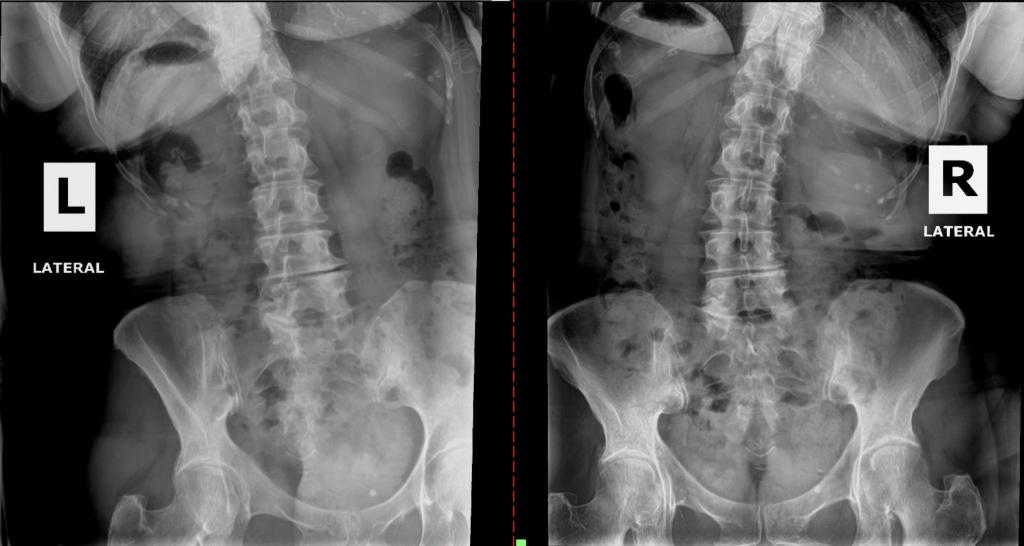

See What We See: Motion-Study X Rays

Most clinics only take still X-rays.

Still X rays show structure, but they miss the most important thing: function.

Motion-study X rays let us watch each spinal segment move frame by frame, revealing hidden joint dysfunction, disc loading, and structural imbalance that often cause true sciatic nerve irritation.

This is why patients who have “tried everything” finally see results here.